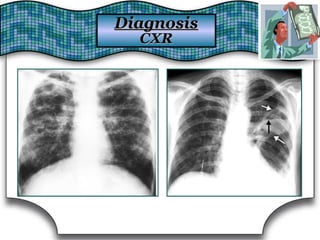

Chest X Ray (CXR)Chest X Ray (CXR)

Chest RadiographChest Radiograph Suggestive DiagnosisSuggestive Diagnosis

Cardiomegaly, increasedCardiomegaly, increased

pulmonary vascular distributionpulmonary vascular distribution

Chronic heart failure, mitral valve stenosisChronic heart failure, mitral valve stenosis

Cavitary lesionsCavitary lesions Lung abscess, TB, necrotizing carcinomaLung abscess, TB, necrotizing carcinoma

Diffuse alveolar infiltratesDiffuse alveolar infiltrates Chronic heart failure, pulmonary edema, aspirationChronic heart failure, pulmonary edema, aspiration

Hilar adenopathy or massHilar adenopathy or mass Carcinoma, metastatic disease, infectionCarcinoma, metastatic disease, infection

HyperinflationHyperinflation COPDCOPD

Lobar or segmental infiltratesLobar or segmental infiltrates Pneumonia, thromboembolism, obstructing carcinomaPneumonia, thromboembolism, obstructing carcinoma

Mass lesion, nodules, granulomasMass lesion, nodules, granulomas

Carcinoma, metastatic disease, Wegener'sCarcinoma, metastatic disease, Wegener's

granulomatosis, septic embolism, vasculitidesgranulomatosis, septic embolism, vasculitides

Patchy alveolar infiltratesPatchy alveolar infiltrates

Bleeding disorders, idiopathic pulmonaryBleeding disorders, idiopathic pulmonary

hemosiderosis, Goodpasture's syndromehemosiderosis, Goodpasture's syndrome